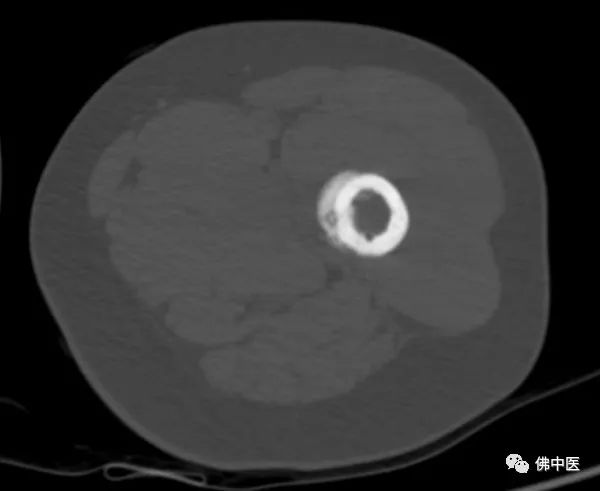

此为横切面图

陈先生左腿股骨病灶